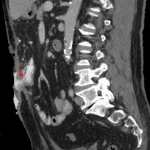

Indication: Abdominal pain and skin drainage

- Contrast material in a tract extending from a small bowel anastomosis in the mid ventral abdomen to the abdominal wall and layering in a large ventral abdominal wall wound

- Additional more superior tracts extending from this anastomosis into the adjacent abdominal wall musculature

- Focal stranding in the lateral right ventral abdomen (this was a site of recent percutaneous drainage)

- Enterocutaneous fistula

Enterocutaneous fistula arising from a small bowel anastomosis in the mid ventral abdomen with adjacent complex sinus tracts.